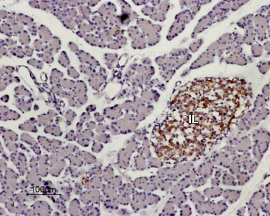

Expression of KISS1R in rat pancreas Immunohistochemical staining of paraffin embedded section of rat pancreas using Anti-Kisspeptin Receptor (extracellular) antibody ( AMM06211G), (1:100). KISS1R staining (brown) appears in Isles of Langerhans (IL). Hematoxilin is used as the counterstain.